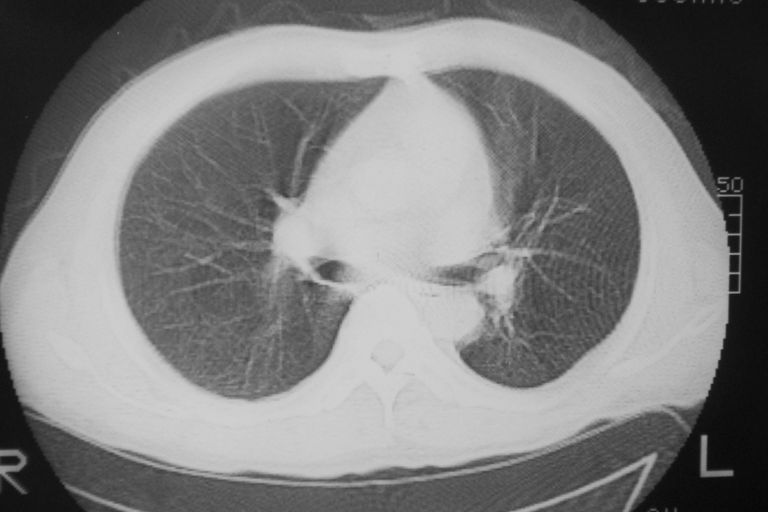

患者 男 50岁 无痛性咯血3天,无其他不适.

左下肺结节状软组织密度影,边缘有毛刺,考虑周围型肺癌。

1 左肺下叶基底段见两结节软组织密度灶, 肺窗边缘见有毛刺征像, 不能排除占位. 2 建议结合临床治疗一周后ct随访在看其结果.

左下肺基底段两个小结节影,边缘毛糙,建议抗炎治疗后复查。

临近胸膜增厚,病变周围肺不清,稍有分叶。结节密度略高,肺、纵隔窗差异不大,肺癌待排。前方还有一个

1 左肺下叶后基底段见结节软组织密度灶,周围见毛刺,建议抗炎后复查,警惕周围型肺癌。

左下肺结节状软组织密度影,一个边缘有卫星病灶,邻近胸膜增厚.另一个有毛刺.心影周围水样密度影环绕.考虑:

1.肺癌可能.肺tb待排.